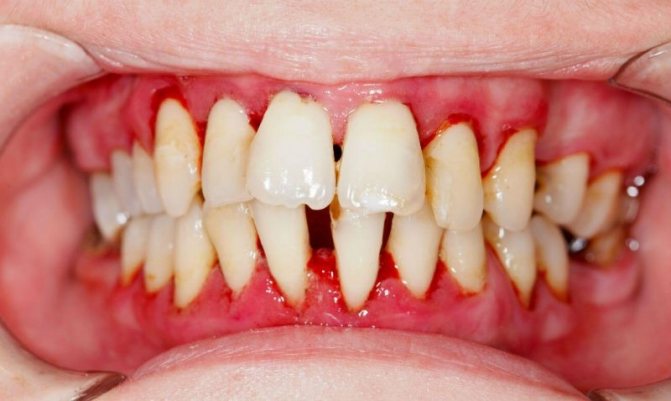

Отличается быстрым развитием и выраженными симптомами. Само разрастание очень болезненно при жевании и дотрагивании, а боль может отдавать в висок. На нем отчетливо видны точечные белесые очаги. Патология сопровождается:

- присутствием отечности десны в месте, где растет эпулис;

- расшатыванием и сильным смещением единиц, прилегающих к опухоли;

- поражением дентальных корневых тканей расположенных рядом зубов;

- кровоточивостью, развивающимся при приеме пищи и гигиенической процедуре;

- появлением трещин и язв;

- развитием высокой чувствительности.

Рецидивы злокачественной опухоли наблюдаются в 20% случаев. В единичных случаях при запущенности состояния отмечались летальные исходы.